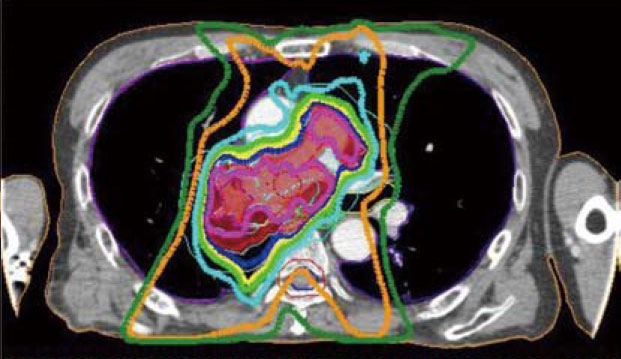

強度変調放射線治療

リニアックのガントリーヘッドに装着されたmulti-leaf collimator(多分割原体絞り)によって作られる異なった照射野の重ね合わせにより、3次元的に複雑な線量分布を得ることを可能にした技法。正常組織の線量を抑えつつ、腫瘍に投与する線量を増加させることが可能になる。

従来の治療(左図)では、腫瘍(赤の塗り潰し部分)に十分に放射線をかけるには正常の肺(黒く見える部分)に多くの放射線照射を余儀なくされるが、強度変調放射線治療(右図)では腫瘍以外へ照射される線量の低減が可能。また、大血管や脊髄へ照射される線量も低く抑えることができ、より効果的に、より安全な治療を提供することができる。

高線量の放射線が照射された範囲

照射された位置は3次元的に記録されており、周囲への影響がないかを数日おきに確認しながら治療を進める。